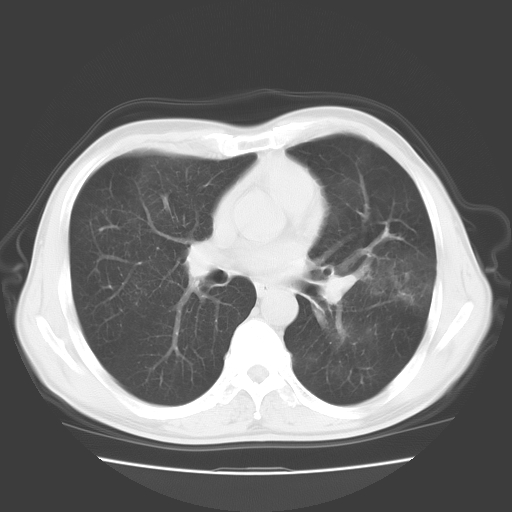

以下是引用随光逐影在2008-11-20 23:02:00的发言:[br]1)考虑左肺上叶周围型肺癌可能性大。2)两肺散在性肺泡积血。[br][br][本贴已被 随光逐影 于 2008-11-20 23:09:31 修改过]

以下是引用drzhang8888在2008-11-20 22:20:00的发言:[br]密集的短毛刺,血管集束,胸膜凹陷,周边型肺癌可能性大,另双肺多发磨玻璃影,考虑感染

以下是引用流浪星在2008-11-20 22:28:00的发言:[br]左肺上叶近外围区见一类圆形结节影,毛刺征、胸膜尾征阳性,临近肺组织见多发渗出灶。考虑1,炎症性病变。 2.周围性肺癌。建议抗炎治疗后复查。

以下是引用qc80012345在2008-11-21 5:53:00的发言:[br]支持;周围型肺癌诊断。增强扫描。